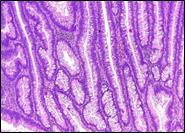

Regarding the endoscopic aspect, colorectal neoplasm presented in the following forms: vegetative formations accounted for 54.6% (n=42) of the 77 patients, vegetative-ulcerative tumor formations were observed in 24.6% (n=19), infiltrative formations with areas of ulceration were described endoscopically in 10.4% (n=8), while the classic infiltrative tumor aspect was detected in 8 patients (10.4%), as summarized in Figure 1.

|

Fig. 1 Endoscopic appearance of colonic neoplasia in patients included in the study |